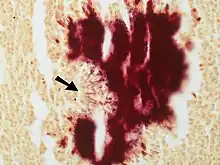

- Colony of Actinomyces surrounded by macrophages.. A Gram stain is needed to see the filamentous organisms. Large colonies of Actinomyces can appear macroscopically as yellow granules whch have been termed "sulfur granules".